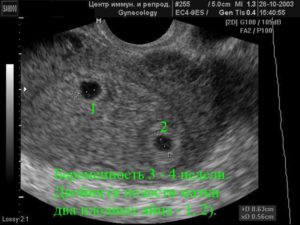

Двойню на УЗИ можно увидеть и определить уже на 4-5 неделе беременности. Как правило, однояйцевые близнецы определяются позже, чем разнояйцевые (не раньше 12 недели).

Самый ранний срок, когда можно выявить, произошло ли зачатие, — 5 недель. В это время врач уже способен разглядеть эмбрионы в матке и определить их количество. На этом сроке начинает формироваться детское сердце, и уже с 8-й недели прослушивается ритм двух или более сердечек. Это также сигнализирует о многоплодной беременности.

На раннем сроке шансы увидеть двойню или тройню намного выше, если малыши многояйцевые.

Признаки такие: у каждого из эмбрионов есть отдельная плацента и плодное яйцо, которые легко разглядеть на мониторе.

Считается, что точно увидеть несколько эмбрионов, можно только при помощи УЗИ. На каком сроке определяют многоплодную беременность? Специалист может увидеть данный факт в 5-6 недель. Но, как правило, ее диагностируют во время первого скрининга в 12 недель.

Самый ранний срок, когда по УЗИ различим плодный мешочек – это 4 недели и 3 дня при условии, что менструальный цикл женщины 28 – 30 дней. Но двойню пока никакой аппарат не определит. Это возможно лишь на 8 акушерской неделе.

Увидеть развитие многоплодной беременности можно на пятой акушерской неделе. При этом разнояйцевые близнецы специалистом определяются раньше, чем однояйцевые.